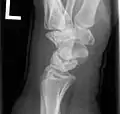

X-ray showing stage IIIB on right wrist, with ulnar impingement.

X-ray on the right wrist showing arthrodesis.